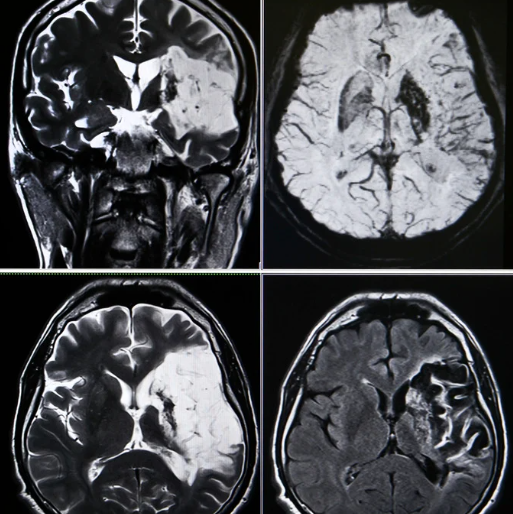

脳血管疾患のリハビリをするうえで、麻痺側上下肢の動きをいかに誘発していくかはとても重要になります。しかしながら、麻痺に対するアプローチも重要ですが、それ以上に日常生活に影響を及ぼす高次脳機能障害の理解を深めなければいけません。本ブログでは失行症状について若手理学療法士や作業療法士にわかりやすいものを解説しています。

半側空間無視を呈する患者様のリハビリの進め方とは?

脳血管疾患において、右半球障害の一部の患者様に半側空間無視を認めることをしばしば経験すると思います。こうした患者様のリハビリにおいて、あなたはどのようなかかわり方を心掛けていますか?エポックオンラインセミナーでは若手理学療法士や作業療法士にわかりやすい講習会を提供しています。